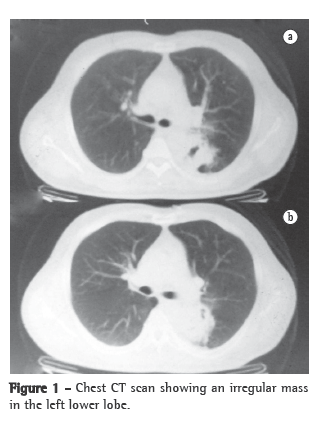

He was initially evaluated as a cardiology patient, due to suspected acute coronary syndrome, which was ruled out through electrocardiography, echocardiography and testing for cardiac enzymes. Therefore, the differential diagnoses were considered. The blood workup showed few eosinophils (2%; 130 cells). A chest X-ray and CT scan of the chest revealed an irregular mass in the upper segment of the left lower lobe, involving the left main bronchus, without involvement of the lymph nodes (Figure 1). Fiberoptic bronchoscopy with transbronchial biopsy revealed no alterations in the bronchial tree. The anatomopathological examination result was normal. Initially, we attempted to rule out TB and pulmonary mycoses. Tests for TB bacillus and fungi in the bronchoalveolar lavage (BAL) were negative, as was the BAL culture for TB and other bacteria. We then opted for thoracoscopy and biopsy. The histopathological examination of the material revealed the following: lung tissue with pronounced fibrosis and intense chronic inflammatory process; multiple granulomas with central areas of suppuration, containing numerous eosinophils; various multinucleated giant cells of foreign-body type and rare non-viable S. mansoni eggs; fibrin deposition; and areas of anthracosis/hemosiderosis (Figure 2).